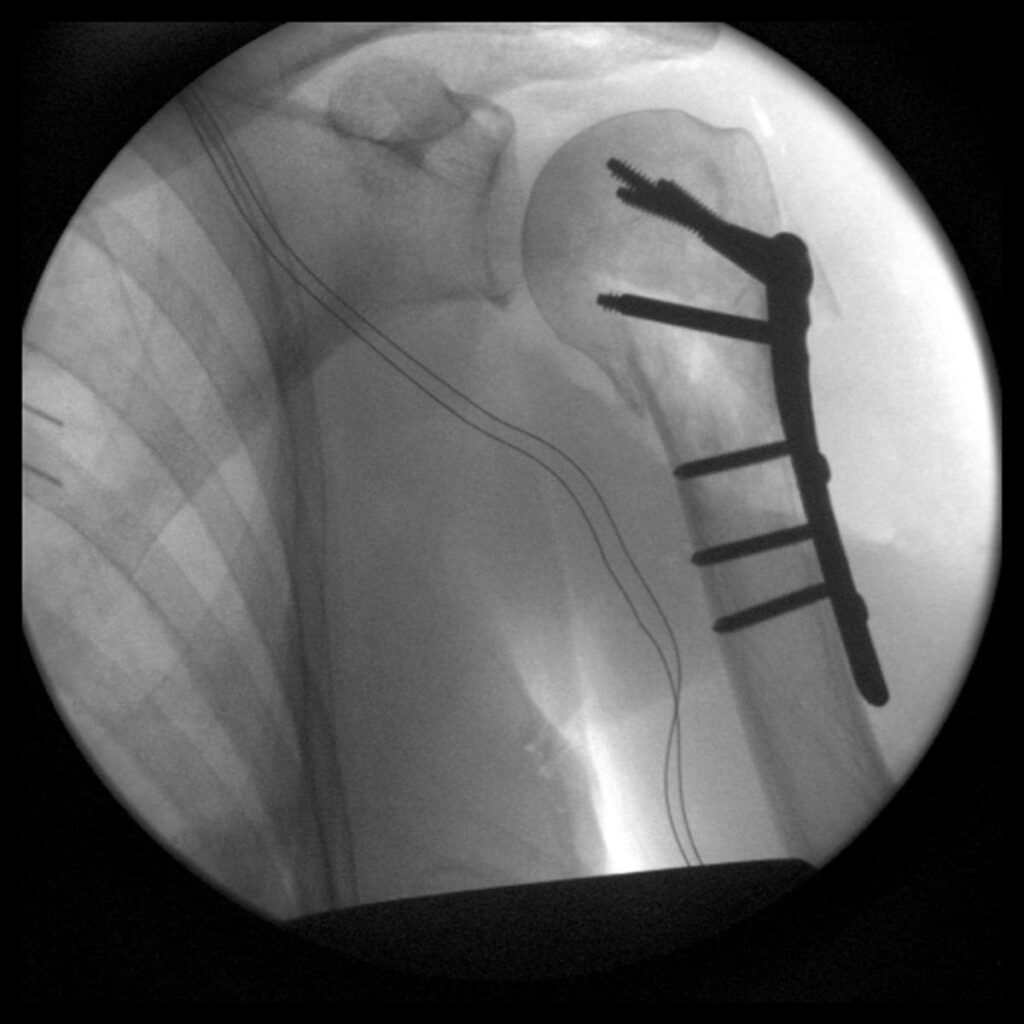

Večina zlomov nadlahtnice se zdravi konzervativno, s kombinacijo imobilizacije in fizioterapije Ljubljana. Pri kompleksnih zlomih ali premikih kosti je lahko potrebna operacija (npr. ORIF ali proteza ramena).

Konzervativno zdravljenje ali operacija